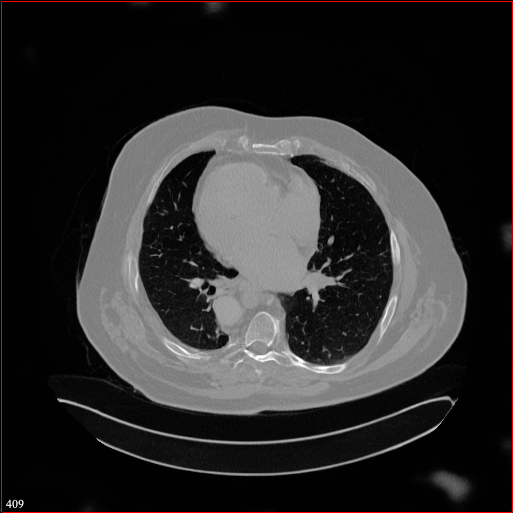

Figure 2: Qualitative comparison across axial (top row), sagittal (middle row), and coronal (bottom row) views. Columns correspond to different methods. MAISI-DDPM and MAISI-v2 in this figure are unconditional synthesis which do not use ControlNet or segmentation maps.

Qualitative Evaluation:

Figure 2 presents representative slices from the axial, sagittal, and coronal planes. GenerateCT (Hamamci et al. 2024) is a 2D model, so it lacks inter-slice consistency, leading to poor image quality in the sagittal and coronal views. MedSyn (Xu et al. 2024) produces noticeably blurry results with mosaic-like artifacts, such as region inside the red box. HA-GAN (Sun et al. 2022) generates visually sharp images but with mosaic-like artifacts, such as region inside the red box. Also, its voxel spacing is not available, which limits its applicability in real-world medical imaging tasks. Moreover, all three methods are restricted to synthesizing small anatomical regions. In contrast, both MAISI and MAISI-v2 are capable of generating high-quality 3D volumes that span larger body regions while preserving fine anatomical details and realistic structure.